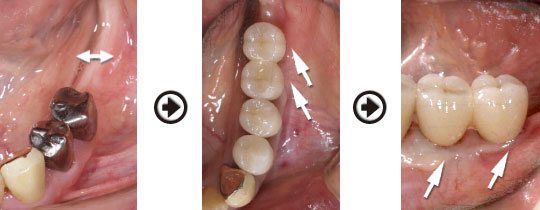

インプラント治療(GBR)過程

前歯の骨が薄い場合でも治療回数と期間はかかりますが、予知性の高いインプラント治療が可能です。

骨を再生させた所にインプラントを植立しました

良い状態を保つため、骨の再生だけでなく歯肉を強化し、清掃しやすい環境に整えます。

骨造成をすることにより清掃性が良くなりメンテナンスしやすくなりました。